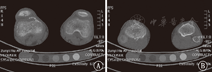

入院后行双膝关节CT检查,结果提示双侧股骨下段干骺端、胫腓骨上段干骺端见多发点、条形高密度影,边缘多发骨性突起,不规则骨质破坏区,两侧髌骨、股骨远端及胫腓骨近端骨骺边缘少许不规则骨质破坏、骨质增生硬化,双膝关节组成骨对应关系未见异常,关节间隙未见狭窄,周围软组织未见肿胀,考虑代谢性疾病、多发骨纤维结构不良、血液系统疾病、类风湿等良性病变(图2)。

注:A:双侧股骨下端干骺端见多发点、条形高密度影,边缘多发骨性突起,不规则骨质破坏区,两侧髌骨及股骨远端骨骺边缘少许不规则骨质破坏、骨质增生硬化;B:双侧胫腓骨上段干骺端见多发点、条形高密度影,边缘多发骨性突起,及不规则骨质破坏区,双侧胫腓骨近端骨骺边缘少许不规则骨质破坏、骨质增生硬化 A:bilateral metaphysis of distal femur showed multiple point or striped high density shadow,multiple osseous protuberances at the edge and irregular bone destruction area.Both sides of the patella and the edge of the epiphysis of the distal femur showed a few irregular fracture damage,hyperosteogeny and osseosclerosis;B:bilateral metaphysis of proximal tibia and fibula showed multiple point or striped high density shadow,multiple osseous protuberances at the edge and irregular bone destruction area.Both sides of the edge of the epiphysis of proximal tibia and fibula showed a few irregular fracture damage,hyperosteogeny and osseosclerosis